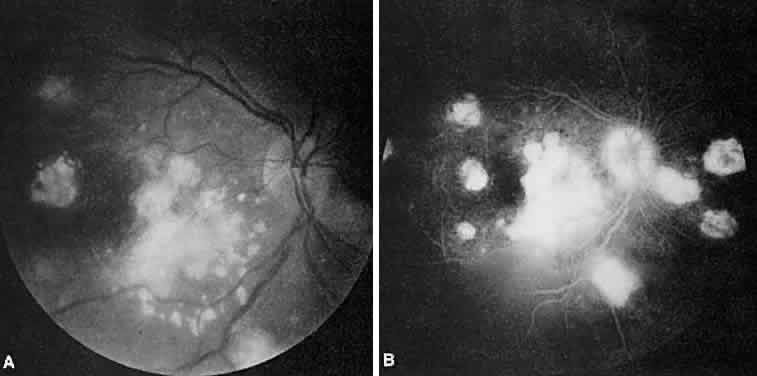

MULTIFOCAL CHOROIDITIS

Multifocal choroiditis may mimic the typical clinical findings of presumed ocular histoplasmosis syndrome (discussed later) and has the additional finding of anterior chamber and vitreous cells. Multiple yellow or gray acute choroidal lesions measuring 50 to 350 μm, periphlebitis, and occasionally retinal neovascularization can be seen. Marked pigmentary disturbances may be seen in the chronic phase (Fig. 11A).

Fig. 11. Multifocal choroiditis. A. Fundus photograph showing pigmentary disturbances. B. Multiple areas of hypofluorescence and hyperfluorescence representing chorioretinal scars with associated atrophic areas. C. Indocyanine green angiogram shows multiple areas of hypofluorescence around the disc, the macula, and the midperipheral fundus. Some of these areas are not visible clinically or on fluorescein angiogram.

On fluorescein angiography (see Fig. 11B), the punched-out lesions show the typical window defects. Acute lesions block early choroidal fluorescence and stain late. Cystoid macular edema and prolonged arteriovenous circulation times may be seen.39 Progressive subretinal fibrosis is a reported sequela that presents as multiple stellar zones of subretinal fibrosis. This fibrosis can be surrounded by multiple atrophic punched-out lesions (Fig. 12).40

Fig. 12. Multifocal choroiditis with subretinal fibrosis in a 26-year-old woman. A and B. Color photographs show hypopigmented lesions representing subretinal fibrosis involving both macular lesions. Multiple punched-out lesions surround the bands of fibrosis. C. Staining of the large stellate fibrous lesion can be seen in the left macula. There are multiple punched-out lesions above and below the macular zone. Leakage from the optic disc and its vessels can also be seen.

ICG angiography shows large hypofluorescent spots in the posterior pole measuring 200 to 500 μm, which did not usually correspond to clinically or fluorescein angiographically detectable lesions (see Fig. 11C). Smaller hypofluorescent spots, less than 50 μm, also may be seen in the posterior pole. Both large and small lesions are best seen in the later phases of the angiogram. Confluent hypofluorescent areas may be seen around the optic nerve in patients reporting an enlarged blind spot on visual field testing.41